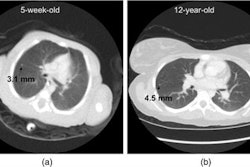

- Use of patient size-specific pediatric CT imaging protocols